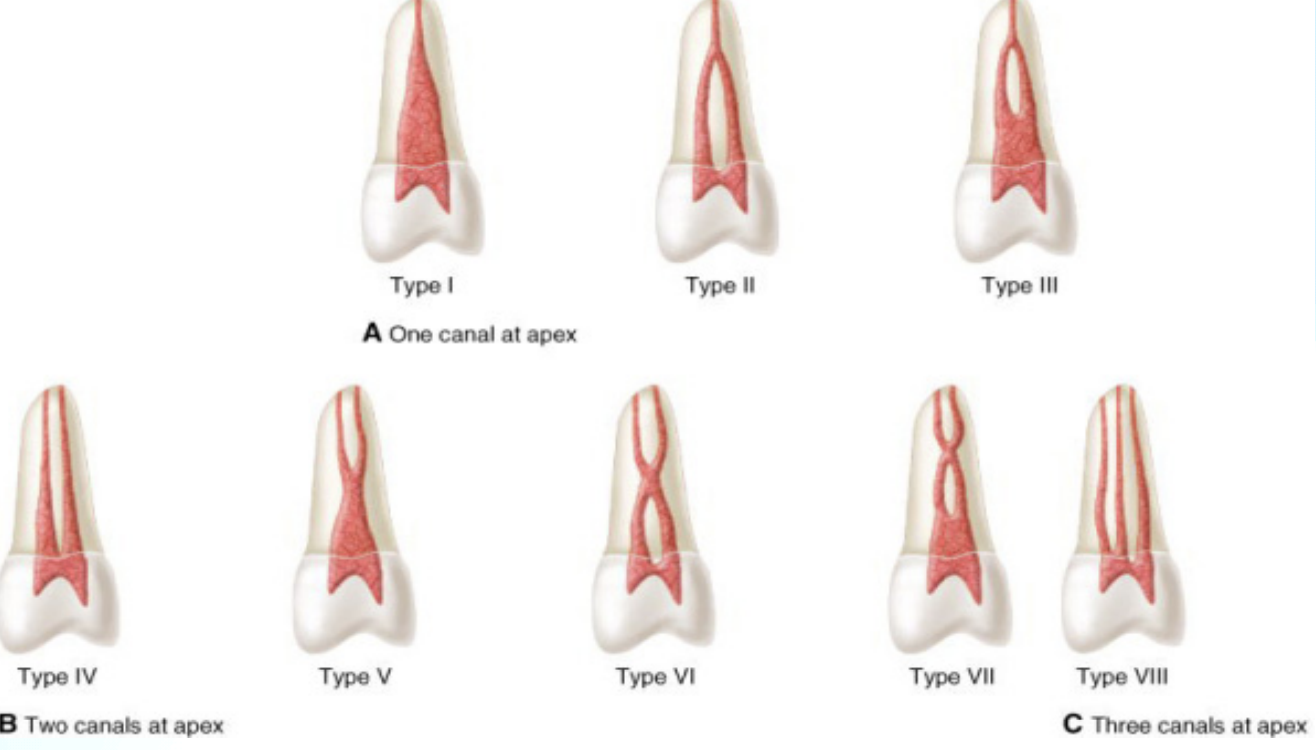

Classification of pulp cavity - vertucci’s classification

One canal at the Apex

Type 1: Single canal extending from pulp chamber to the apex

Type 2: Two canals leave the pulp chamber and join to form a single canal at the apex.

Type 3: One canal leaves the pulp chamber, divides into 2 canals, and then reconverts to form a single canal at the apex.

Two canals at the Apex

Type 4: Two separate canals leave the pulp chamber

Type 5: leaves pulp chamber as one, and then divides into 2 separate apical foramina

Type 6: Two separate canals leave the pulp, they merge as one in the middle body of the root but then re-divides short of the apex

Type 7: Single canal leaves the pulp chamber, divides into two, then rejoins in the middle, then finally re-divides into 2 canals short of the apex

Three canals at the Apex

3 separate and distinct canals extend from pulp chamber to the apex